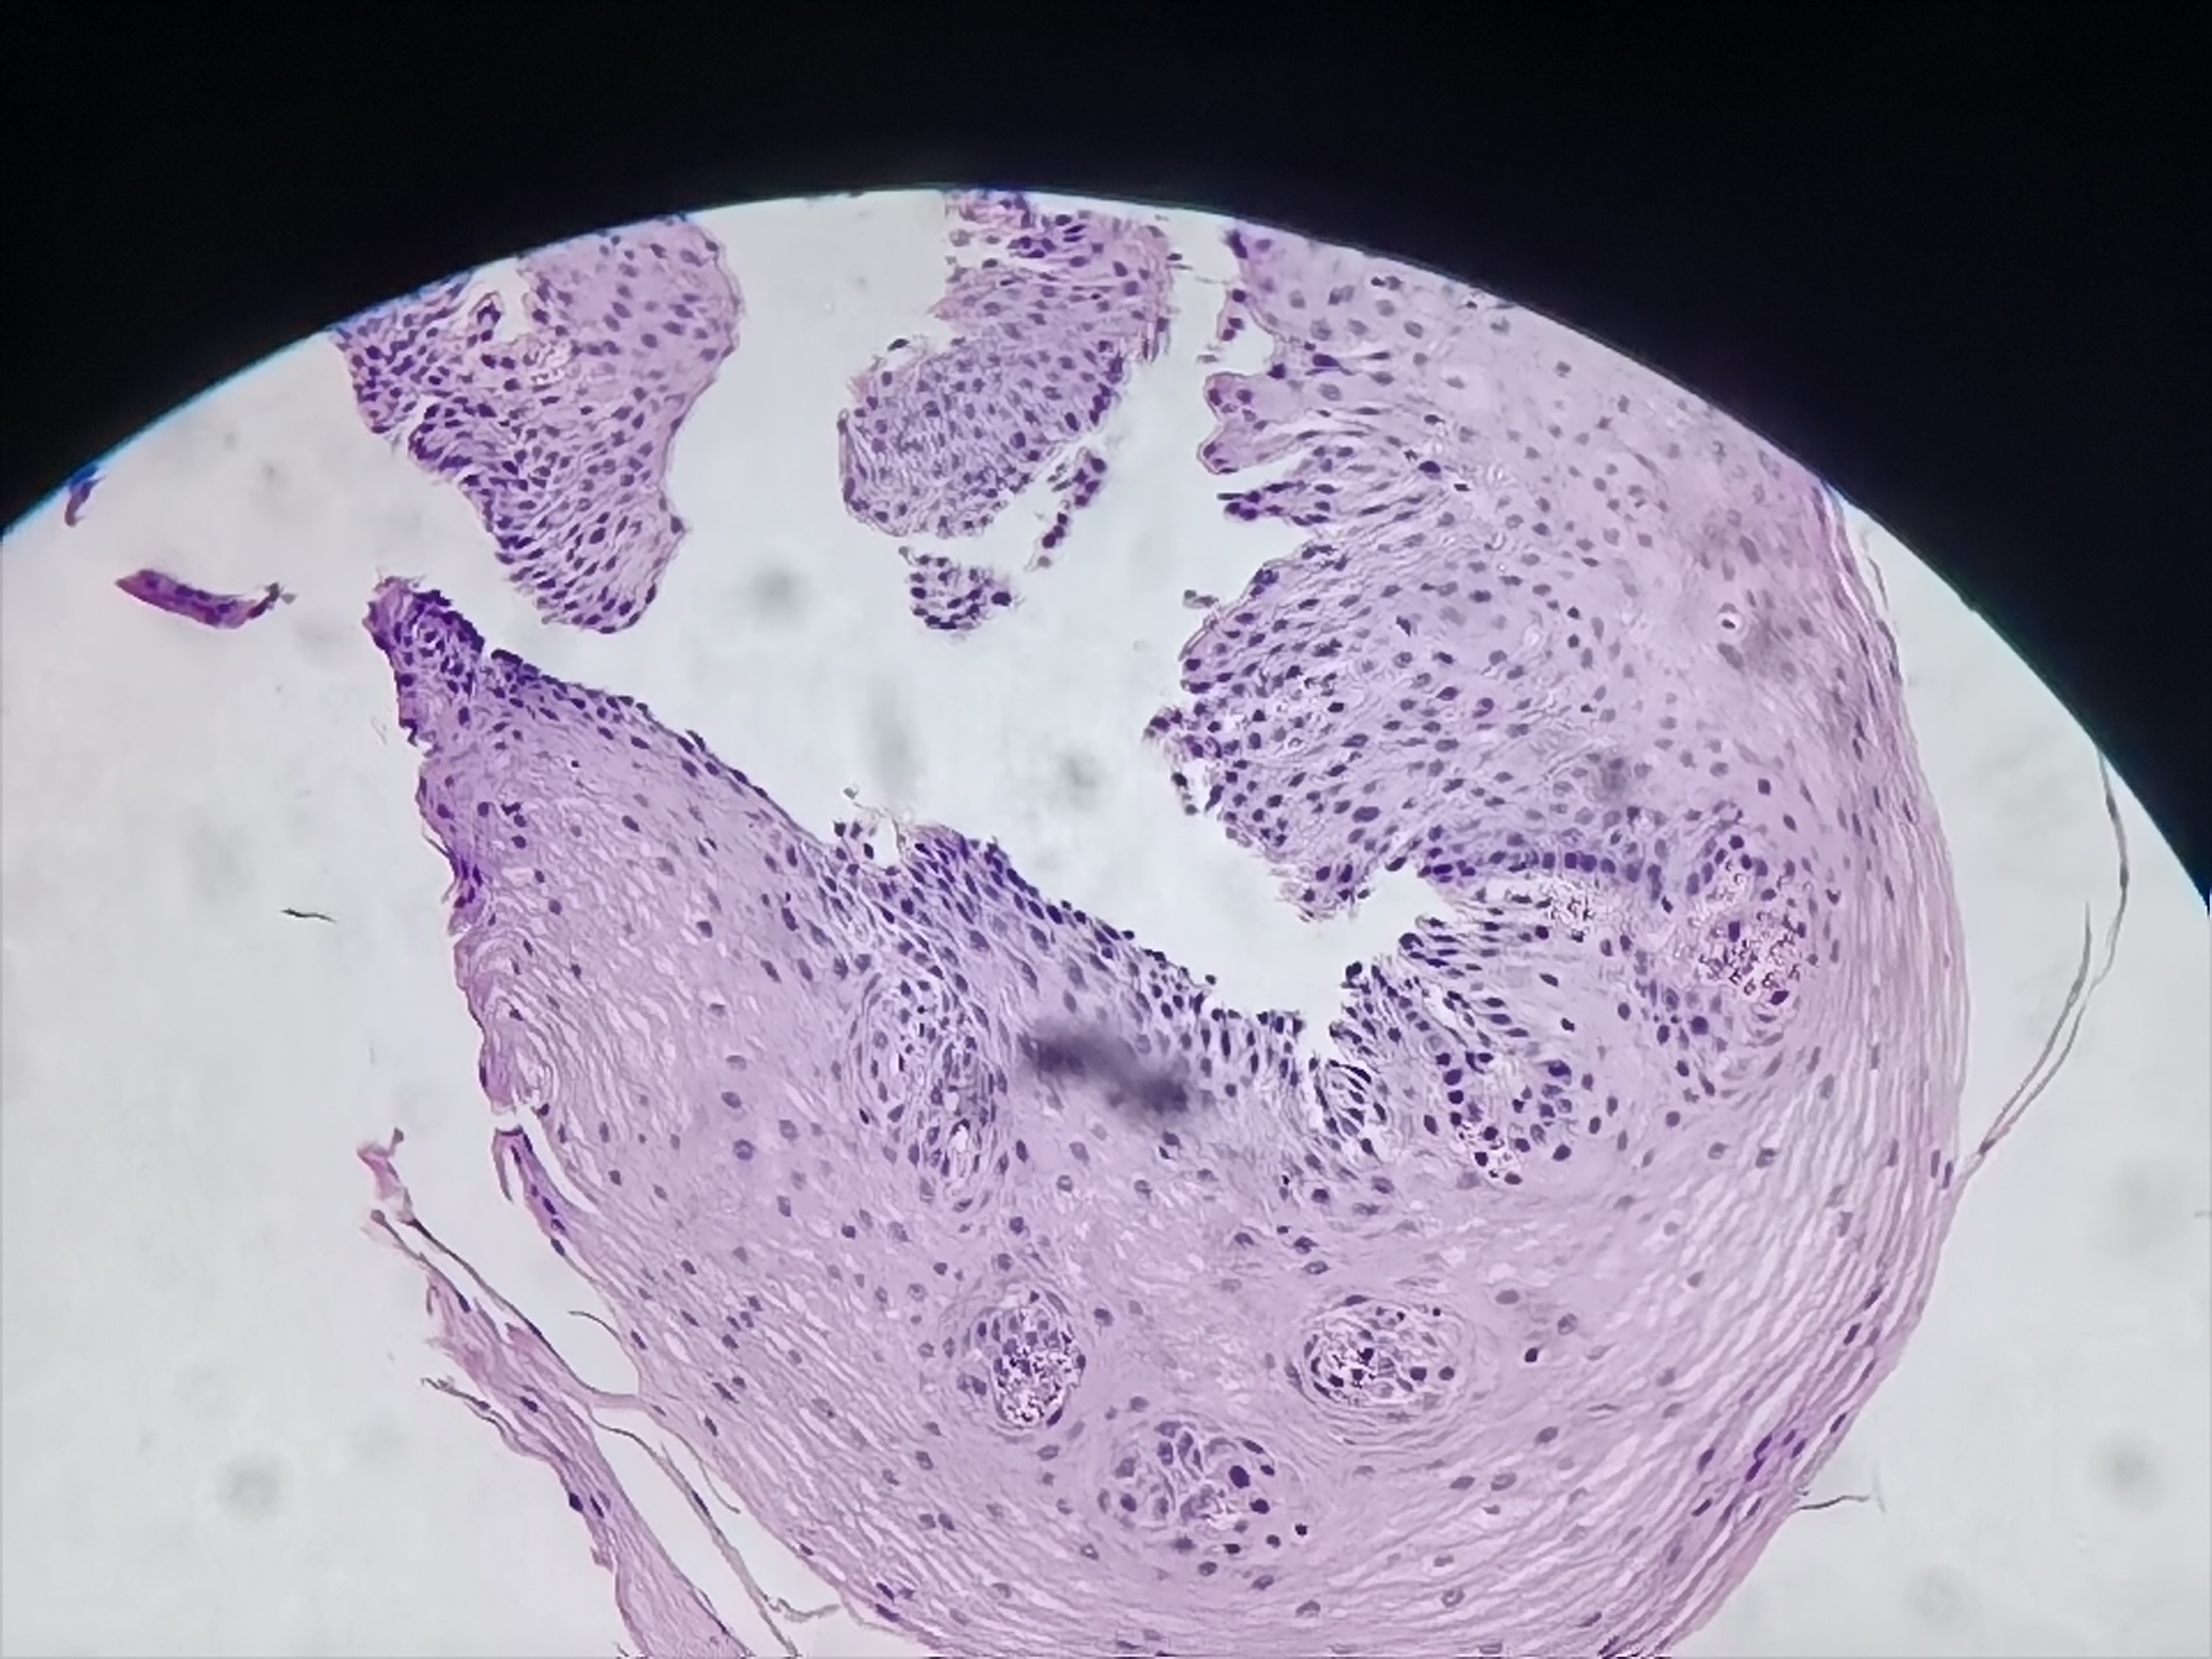

食管活检

性别

女

年龄

69岁

距门齿30cm处可见粘膜粗糙

食管粘膜活检

灰白色组织2块

高级别瘤变

粘膜慢性炎。